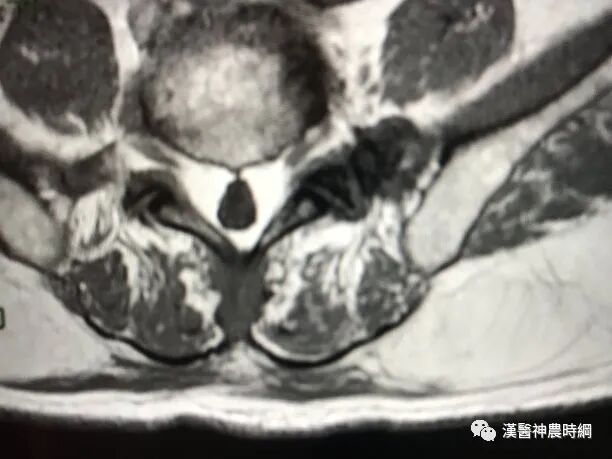

病变位于真皮深层、皮下层,呈球形、结节状或分叶状外观。瘤体主要由成熟的脂肪细胞构成,包膜菲薄而完整。纤维组织由包膜向瘤体内分布纤维性间隔,形成小梁分支,将瘤体分隔成大小不等、比正常脂肪小叶为大的小叶,切面浅黄色、质软,脂肪油腻状(图1)。

小梁内可见血管分布,毛细血管随小梁分支而进入瘤体。瘤体的血管分布常不均匀,在瘤体表面或一侧的血管较多。

当纤维组织增多达瘤体切面一半左右,即称纤维脂肪瘤。若血管成分增多达瘤体切面一半左右,则称血管脂肪瘤。

镜下可见毛细血管内皮细胞增生,管腔狭窄,有时伴血栓形成。瘤细胞大小、形态,类似正常脂肪细胞,有时可见灶性黏液变性。该区域出现泡沫细胞、小星形细胞、梭形细胞伴基质黏液样,称为黏液脂肪瘤。肿瘤偶见出血、坏死、钙化、液化或黄色瘤样变。